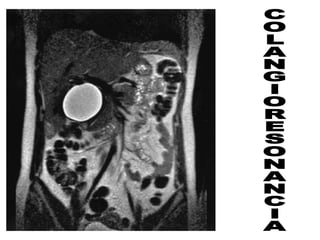

• El Diagnóstico es mejor con Ecografía ,

Colangioresonancia y/o Colangiografía

intraoperatoria